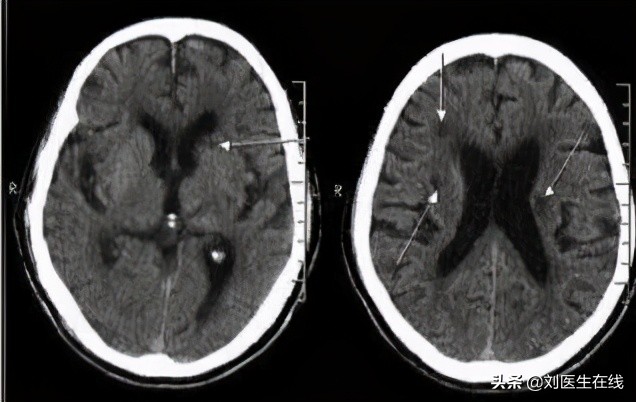

医生在询问王阿姨服药的相关问题,结合CT检查,排除了脑出血。

脑梗依据病因可主要分为大动脉粥样硬化、心源性栓塞和小动脉闭塞三种。

其中,心源性栓塞,也就是堵塞脑部血液循环的这个栓子是来自于心脏部位的。

房颤则是心源性栓塞最常见的原因,房颤时,人体心房的有效收缩功能会明显减弱,给心室的供血量就会变少,同时血液容易在心房内阻滞形成血栓,当栓子脱落之后会随着主动脉进入全身,进而到达颈内和颅内动脉,堵塞脑血管导致脑梗发生。